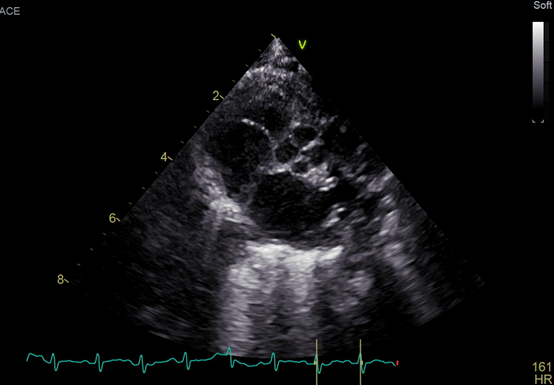

An echocardiogram showed a large ventricular septal defect overriding the aorta with septum and quadricuspid aortic valve (Figure). No stenosis or regurgitation was observed though the valve. The valve consisted of 3 equal cusps and a smaller one, which is type B according to the Hurwitz and Roberts classification (Video). Fluorescent in situ hybridization was negative for 22q11 deletion. The patient established feeds and was discharged home with the plan to have regular follow-ups.